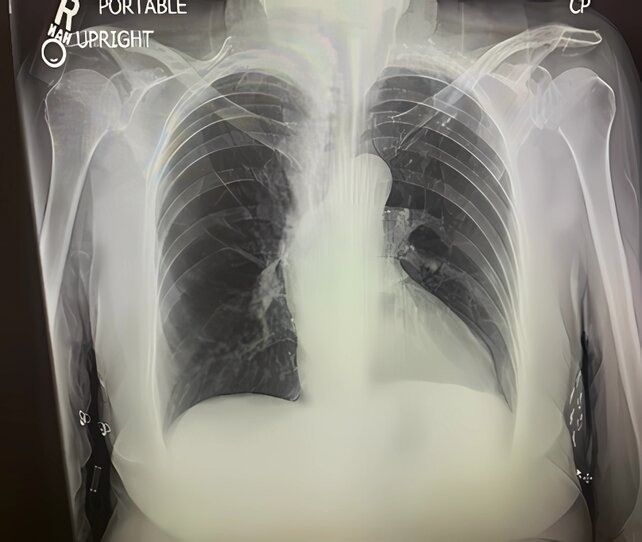

A chest X-ray revealed clear lung fields without pulmonary infiltrates or congestion. However, a moderate left pleural effusion was noted, evidenced by blunting of the left costophrenic angle. The cardiac silhouette appeared normal in size and contour (Figure 2).

Figure 2. Frontal chest radiograph showing clear lung fields without infiltrates or signs of pulmonary congestion. A moderate left pleural effusion is noted, evidenced by blunting of the left costophrenic angle; cardiac silhouette is normal in size.